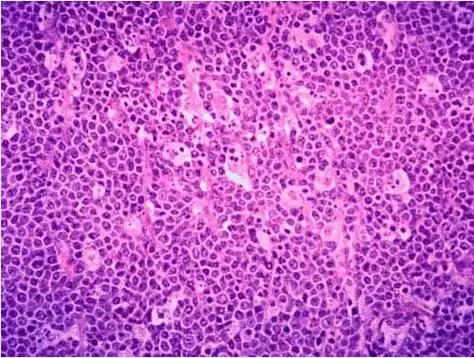

伯基特淋巴瘤的病理诊断和鉴别诊断(一)

镜下观如图所示,以下叙述中错误的是 ( )

镜下观如图所示以下叙述中错误的是